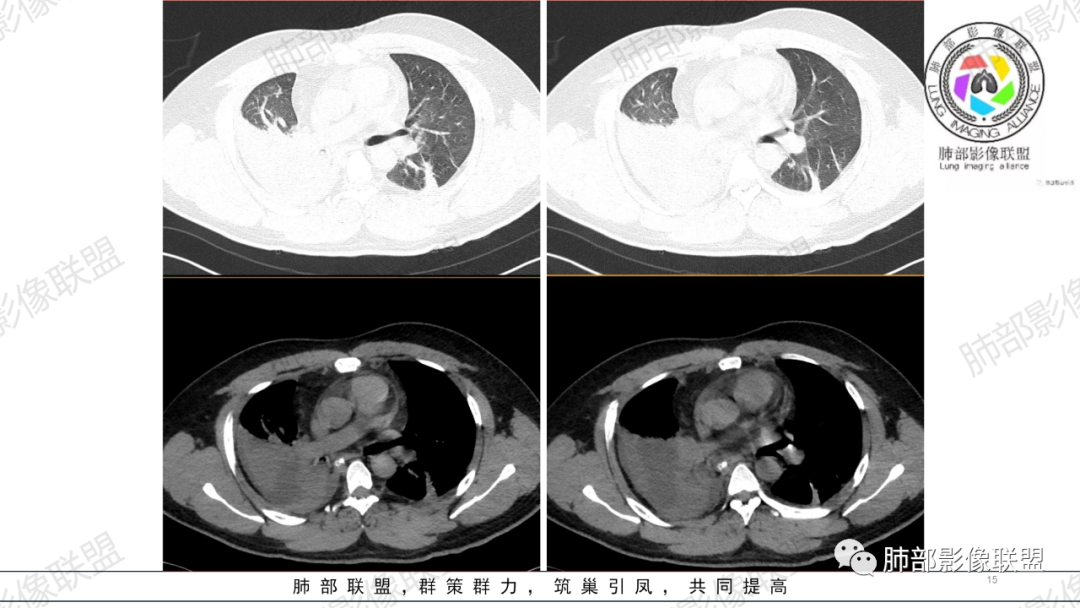

支气管痰栓或粘液阻塞,临床上并不少见,本例患者有腹部手术或胸部外伤肋骨骨折病史,其原因多是长时间采取一种被动体位,因怕疼痛而不敢咳嗽导致痰液引流不畅,自主排痰有一定的困难,导致痰液形成后不能及时排除。滞留痰液集聚形成痰块,混合坏死组织,部分形成痰栓。痰栓附着在气道壁上,局部气道变窄,如果不及时通畅气道,导致原来肺部、胸腔病变加重或出现新的病变,严重者可致局部气道闭塞,相应的肺叶出现肺不张CT上支气管粘液栓形态多样,可呈圆形,类圆形,条状、指套状、葡萄串状等。